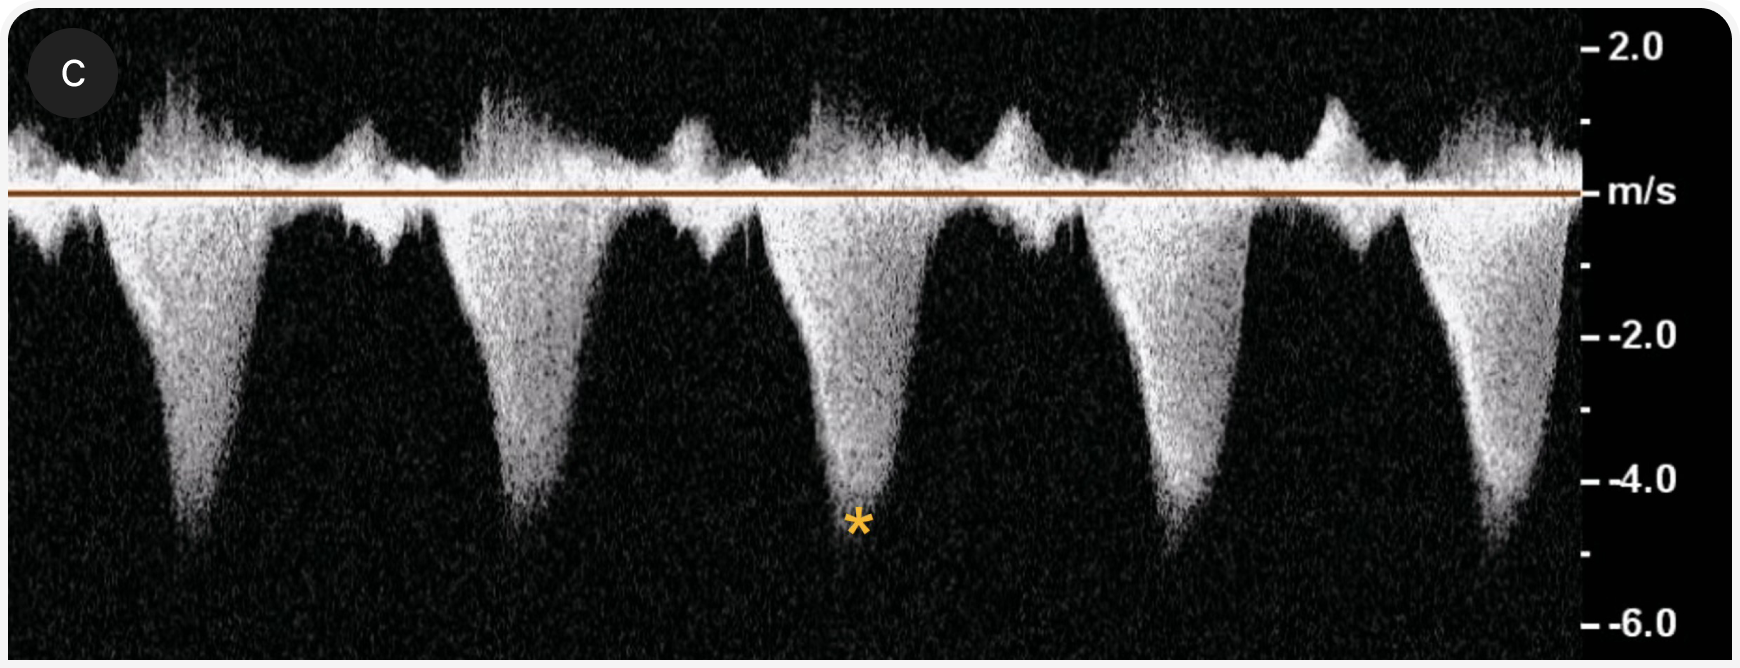

3. Наличие обструкции ВТЛЖ

Обструкцию ВТЛЖ можно оценить с помощью двухмерной эхокардиографии, в М-режиме, при допплерографии с цветовым картированием потока и спектральной допплерографии (Рисунок 3c). SAM можно визуализировать как в двумерном, так и в М-режиме. При допплерографии с цветовым картированием потока определяют турбулентность в ВТЛЖ и, возможно, митральную регургитацию. При спектральной допплерографии возможно оценить скорость кровотока через ВТЛЖ , если поток хорошо визуализируется; при динамической обструкции в допплерографическом профиле часто выявляют двухфазное ускорение (в форме классической турецкой сабли — ятагана).